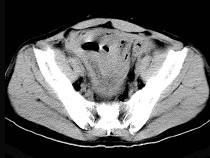

问题 58岁,间断腹部隐痛9个月,贫血3个月,近日加重并伴有柏油样便,CT所见如图,最可能诊断是()

选项 A.小肠淋巴瘤 B.小肠恶性间质瘤 C.小肠重复畸形 D.小肠癌 E.小肠淋巴肉瘤

答案 E